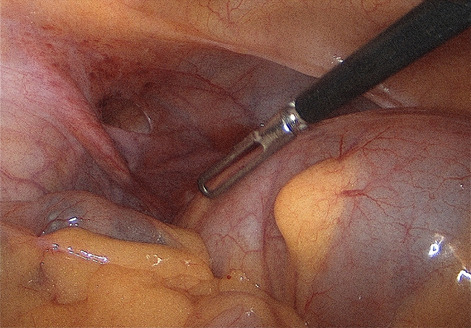

Result: The comparative analysis of the data shows a decrease in the number of presentations in ESU of AC cases during the pandemic, compared to the previous year, most often due to patients' fear of contacting the virus in the hospital environment. The median time between the onset of symptoms and the presentation in the ESU: 2020 – 14 days, 2019 – 5 days. Forms of moderate and severe AC predominated in the pandemic: GradeI—14.28%; GradeII—57.14%; GradeIII—28.57%. In 2019 GradeI—66.39%, GradeII—27.73%, GradeIII—5.88%. Laparoscopic cholecystectomy was attempted for all patients from the beginning, but the complications identified during surgery and severe forms led to a conversion rate in 2020 of 14.28%, compared to 5.88% in 2019. The severity of the cases is also observed in the postoperative complications encountered (perihepatic abscess Fig. 2. Figure 2, wound infection, bile leak; 2019—5.04%, 2020—23.21%), which required surgical reinterventions to solve them (2019: 2.52%, 2020: 10.71%). The number of deaths was significantly higher in 2020 (5.35%), compared to 2019 (0.84%).

Conclusion: Neglecting this pathology frequently encountered in ESU can lead to life-threatening complications and therefore we argue that a laparoscopically resolved cholecystectomy even in the "Covid19 era" remains the gold standard, guaranteeing the best results. Initially attempted conservative treatment may be a solution, but in the long term it can lead to severe complications and high costs.